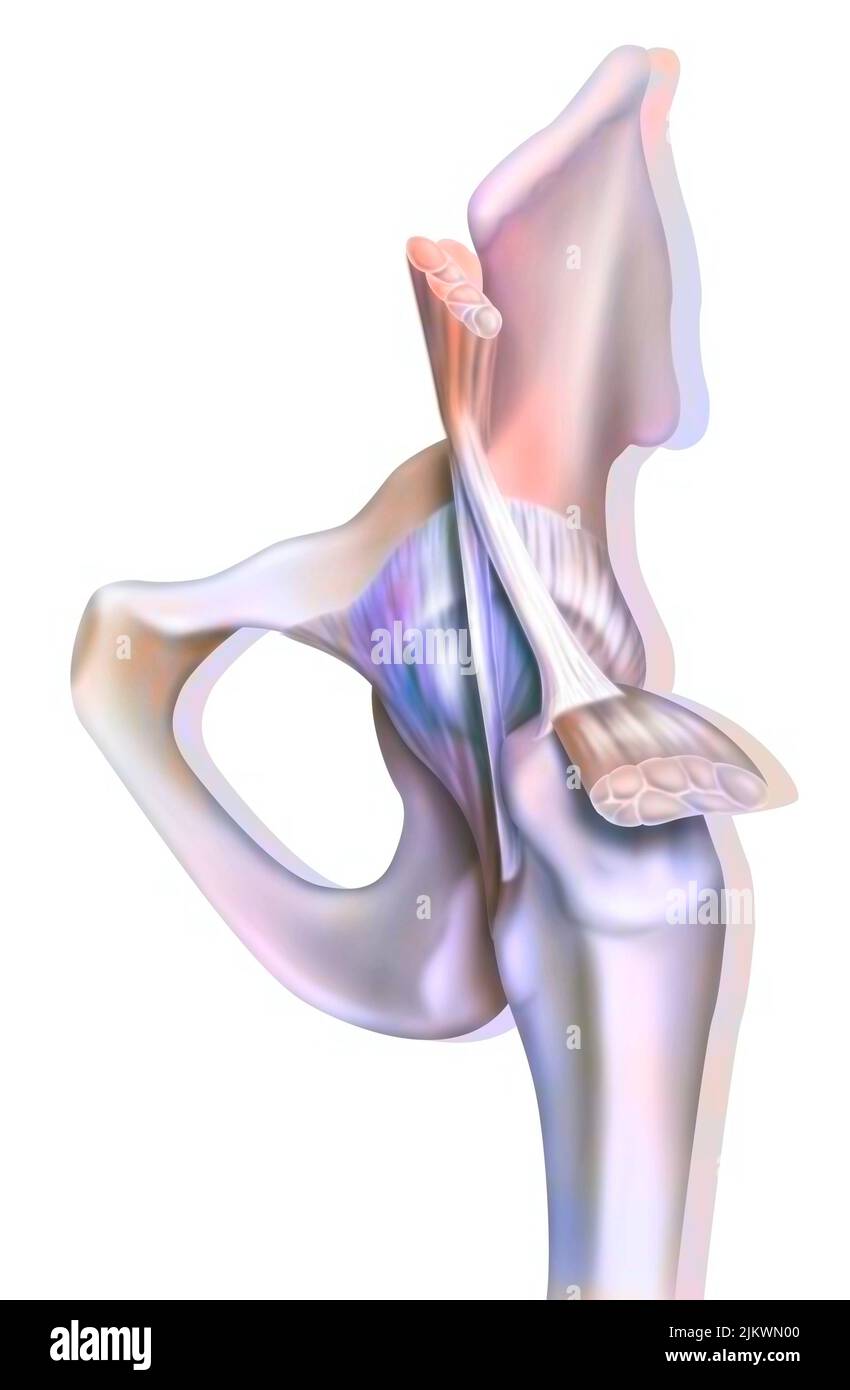

Anatomie de l'articulation coxofémorale (hanche) avec les muscles, les tendons. Banque D'Imageshttps://www.alamyimages.fr/image-license-details/?v=1https://www.alamyimages.fr/anatomie-de-l-articulation-coxofemorale-hanche-avec-les-muscles-les-tendons-image476923664.html

Anatomie de l'articulation coxofémorale (hanche) avec les muscles, les tendons. Banque D'Imageshttps://www.alamyimages.fr/image-license-details/?v=1https://www.alamyimages.fr/anatomie-de-l-articulation-coxofemorale-hanche-avec-les-muscles-les-tendons-image476923664.htmlRF2JKWN00–Anatomie de l'articulation coxofémorale (hanche) avec les muscles, les tendons.

Anatomie de l'articulation coxofémorale (hanche) avec les muscles, les tendons. Banque D'Imageshttps://www.alamyimages.fr/image-license-details/?v=1https://www.alamyimages.fr/anatomie-de-l-articulation-coxofemorale-hanche-avec-les-muscles-les-tendons-image476923600.html

Anatomie de l'articulation coxofémorale (hanche) avec les muscles, les tendons. Banque D'Imageshttps://www.alamyimages.fr/image-license-details/?v=1https://www.alamyimages.fr/anatomie-de-l-articulation-coxofemorale-hanche-avec-les-muscles-les-tendons-image476923600.htmlRF2JKWMWM–Anatomie de l'articulation coxofémorale (hanche) avec les muscles, les tendons.

Articulation osseuse de la hanche sans et avec la capsule de l'articulation coxofémorale. Banque D'Imageshttps://www.alamyimages.fr/image-license-details/?v=1https://www.alamyimages.fr/articulation-osseuse-de-la-hanche-sans-et-avec-la-capsule-de-l-articulation-coxofemorale-image476923594.html

Articulation osseuse de la hanche sans et avec la capsule de l'articulation coxofémorale. Banque D'Imageshttps://www.alamyimages.fr/image-license-details/?v=1https://www.alamyimages.fr/articulation-osseuse-de-la-hanche-sans-et-avec-la-capsule-de-l-articulation-coxofemorale-image476923594.htmlRF2JKWMWE–Articulation osseuse de la hanche sans et avec la capsule de l'articulation coxofémorale.